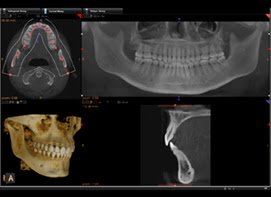

Dental Cone Beam Computerized Tomography [3D X-rays]

Our latest addition to in-office technology is Cone Beam Computerized Tomography imaging which provides best-in-class cephalometric image quality with Ultra-high resolution and very low-dose radiation.

Dental CBCT images provide three-dimensional (3-D) information, rather than the two-dimensional (2-D) information provided by a conventional X-ray image. This may help with the diagnosis, treatment planning and evaluation of certain conditions. At our practice, this technology provides us with an ideal solution for single implant placements, as well as dental implant planning, root canal diagnosis, orthodontic evaluation, evaluation of jaws and face and diagnosis of dental trauma The actual CBCT scan takes approximately 20 seconds. The total appointment time (including positioning, scanning, reconstruction, and scan verification) is less than an hour. Some of the advantages of the CBCT are